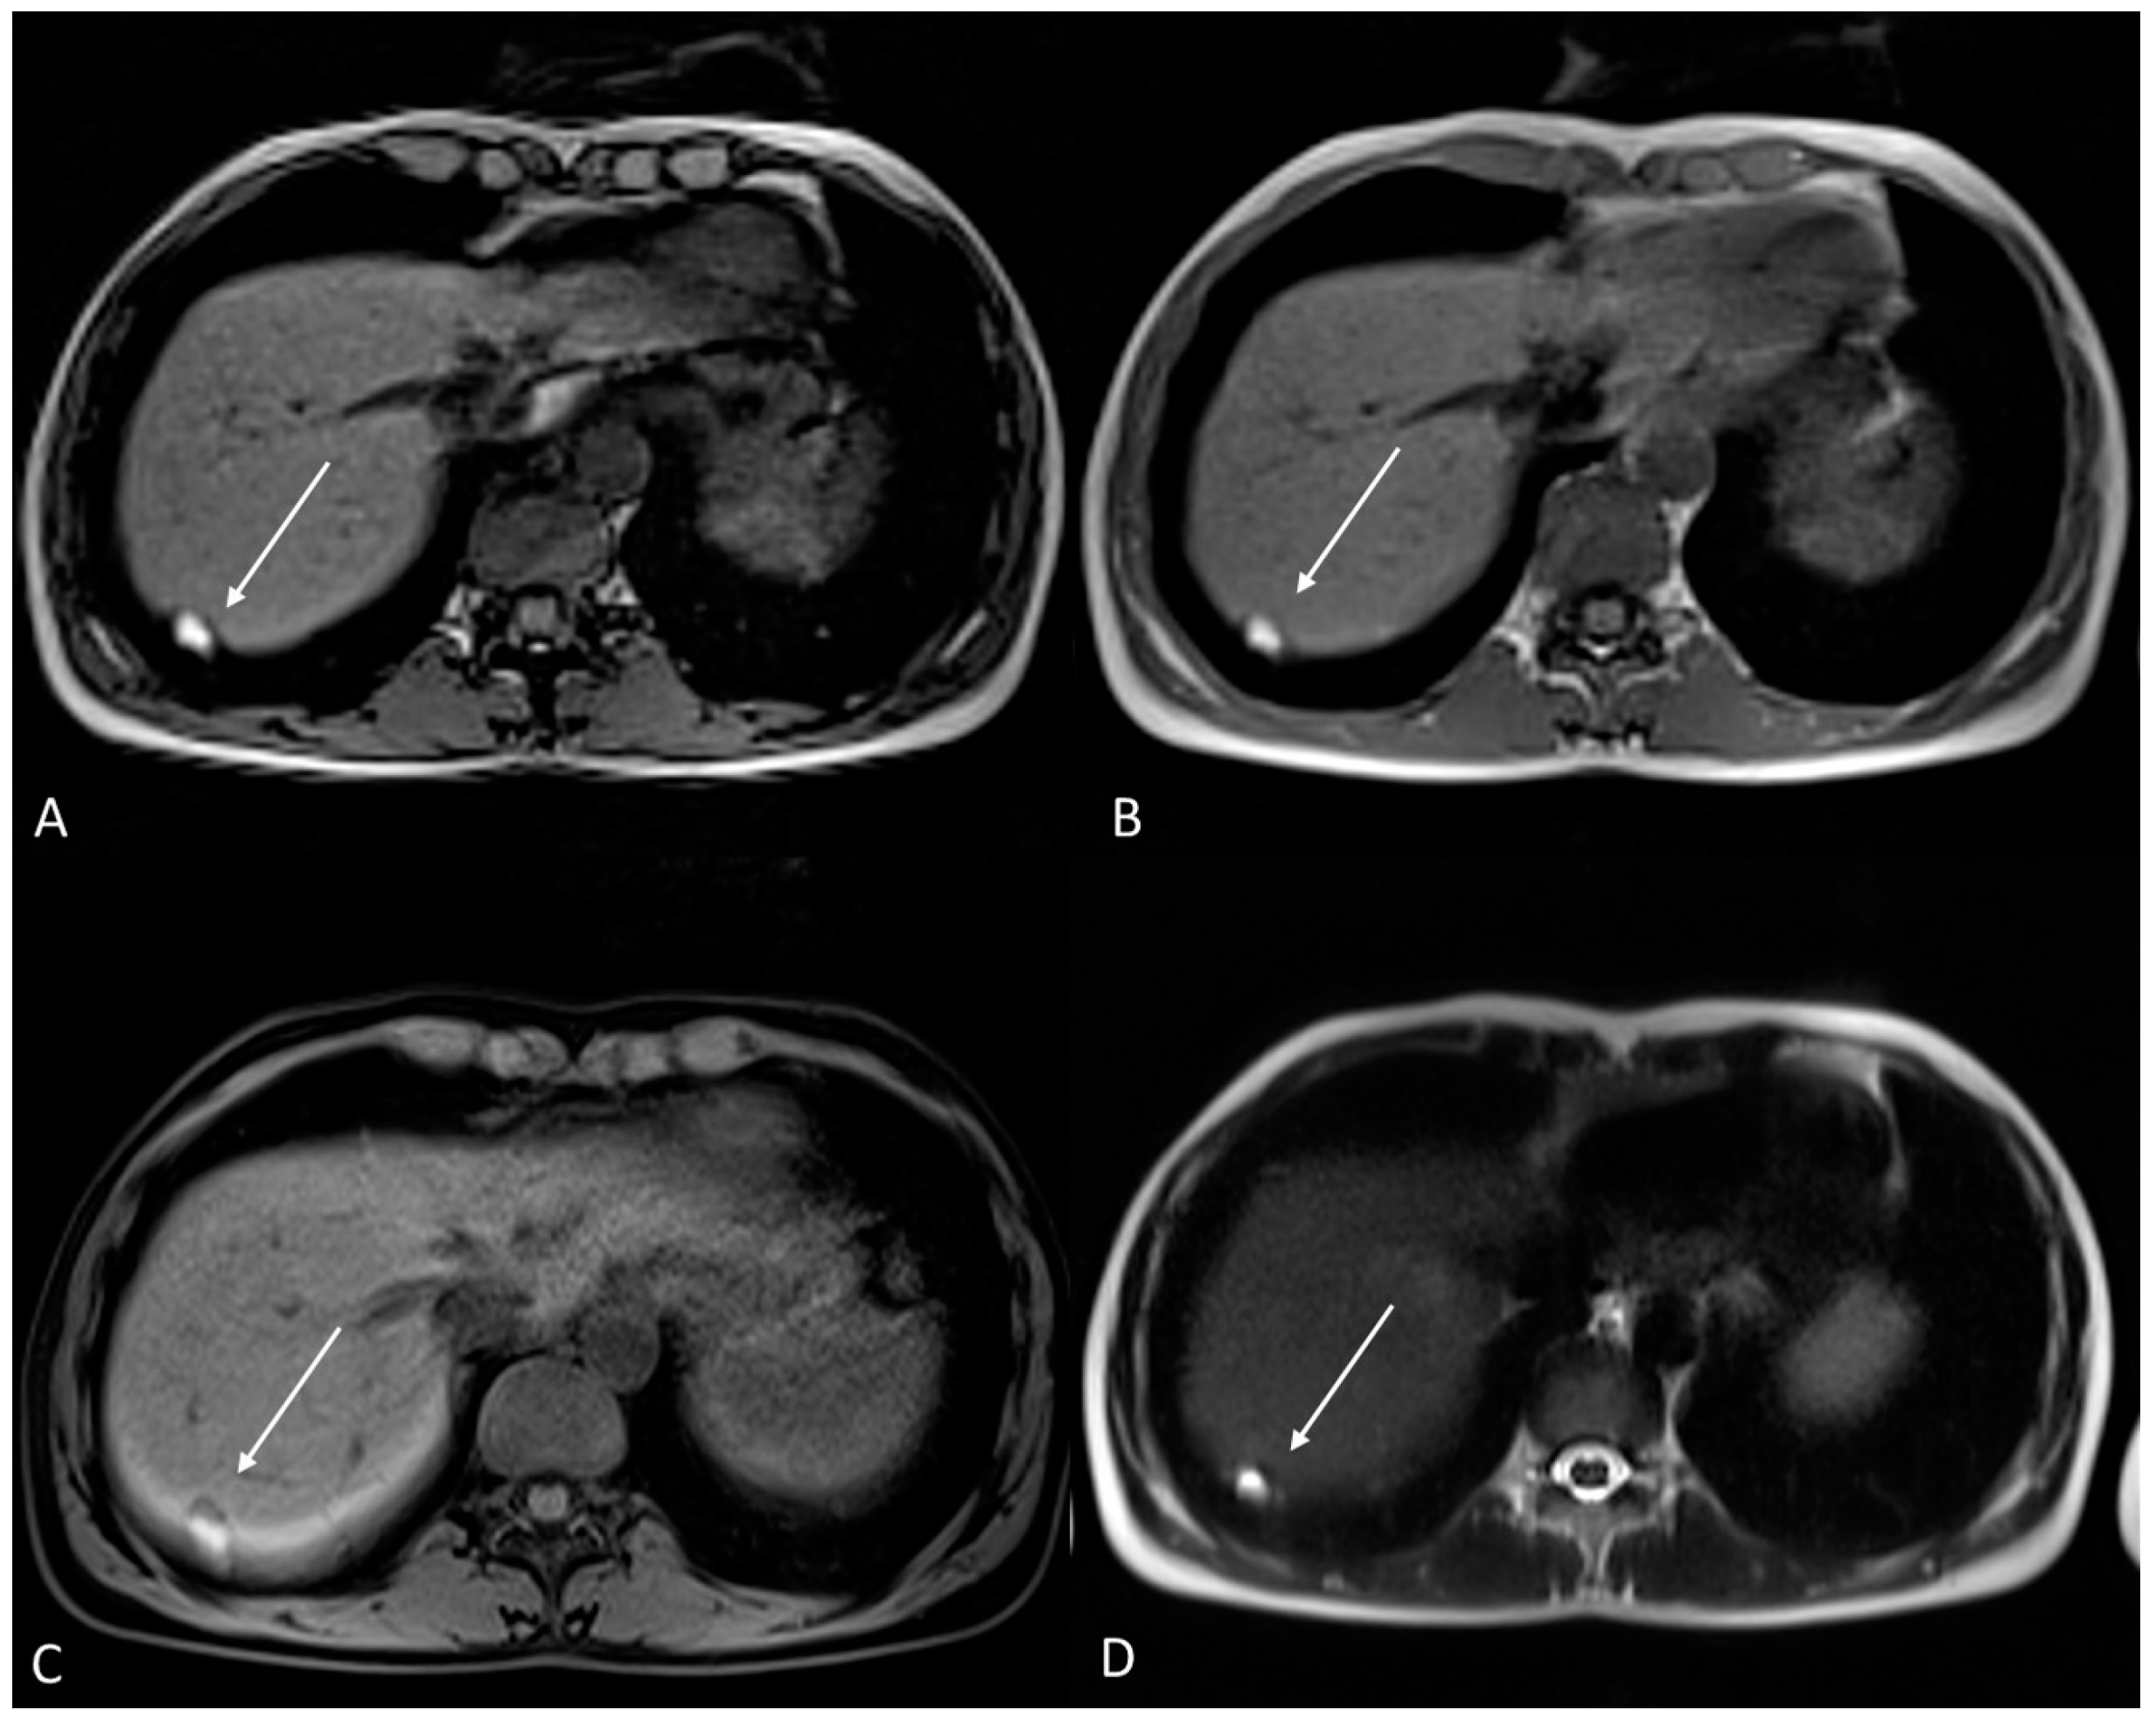

Figure 9.

Diffuse internal and external adenomyosis in a 37-year-old female. (A) Sagittal T2WI; (B) Axial T2WI. Diffuse internal adenomyosis as demonstrated by diffuse hypertrophy of the JZ (white arrowhead in (A,B)), subserosal hypointense ill-defined mass in the posterior myometrium consistent with external adenomyosis (white dotted arrows in (A,B)), with associated deep endometriosis of posterior compartment. Left endometrioma with T2 dark spot sign (white arrow in (B)).

The aforementioned criteria serve as indirect indicators that can aid radiologists in reporting cases of internal adenomyosis (Figure 9). On the other hand, direct criteria include the observation of cystic areas (hyperintense on T2WI) and/or hemorrhagic foci (hyperintense on fat-suppressed T1WI and T1WI) within the inner layer of the myometrium [67,69] (Figure 10).